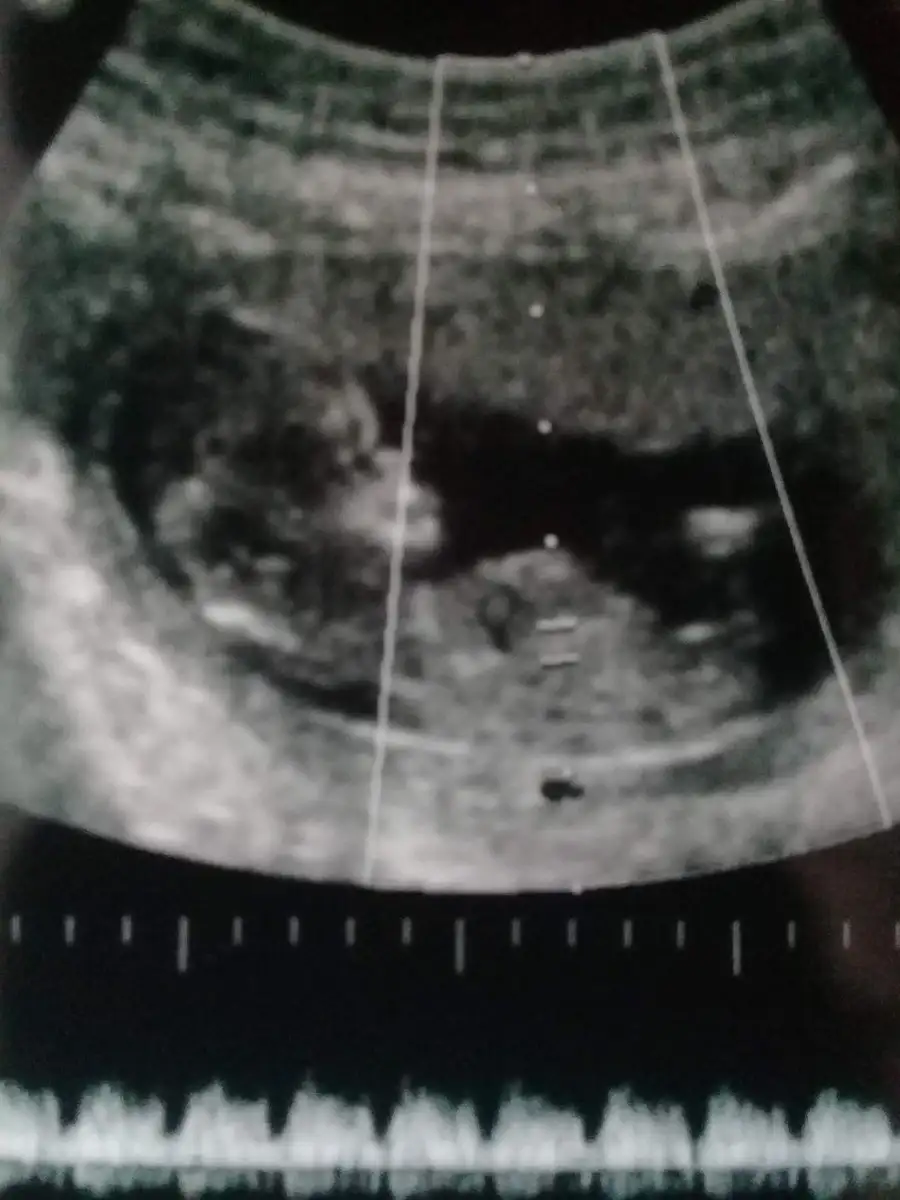

Benimde 6 7 haftalıkken kese görüntüsü tahmin edermisiniz cinsiyetini?

• 1548419951174-657122974.webp

1548419951174-657122974.webp

36,9 KB · Görüntüleme: 90